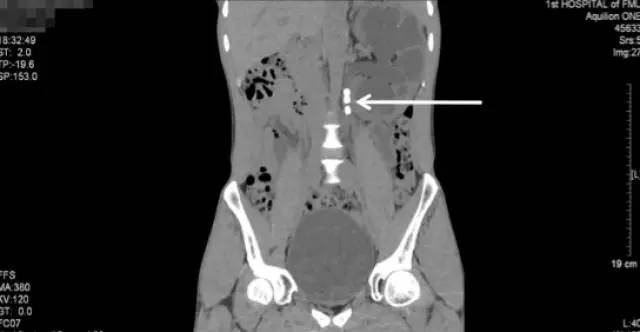

第二次来福建医科大学附属第一医院复查KUB检查结果

通过与4个月前的片子对比,我们可以看到虽然经过了两次手术,但是左肾区仍然遗留了大量而且分散的结石,甚至输尿管上段都有结石卡住(白色箭头所指结石),所以其症状仍然反复。

从他复查的这个KUB上,我们可以看到,左肾仍然有很多结石,而且还有结石掉到左侧输尿管上段引起了梗阻。这种结石如果不取干净,他肾脏里的结石就会时不时掉下来一颗两颗的,堵住输尿管,最终一定会把这个肾脏搞坏掉,我果断通知患者立马住院。

入院后进一步行泌尿系CT平扫+三维重建

(白色箭头提示的就是多发的残留结石)

泌尿系CT:红箭头示左肾重度积水;白箭头示多发结石

白色箭头所指就是引起梗阻的掉到输尿管的结石

CT三维重建图像可见左肾明显增大、扩张积水、多发结石